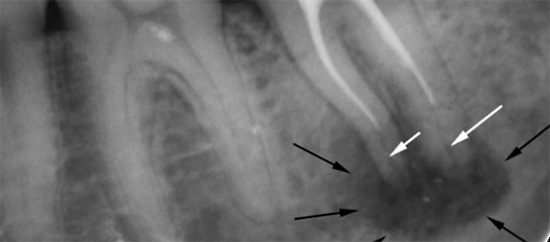

Como parte do diagnóstico diferencial, o eletrodontodiagnóstico (EDI) é talvez o método mais informativo e permite determinar com precisão não apenas o estágio crônico da inflamação com degeneração fibrosa dos tecidos dentro do dente, mas também distingui-lo de outras formas crônicas (gangrena pulpar e sua hipertrofia). Como uma polpa saudável começa a responder a uma corrente de 2-6 μA (com cárie profunda - até 20 μA), todos os desvios sérios desse valor indicam um estado particular de inflamação da polpa. Com pulpite fibrosa, o "nervo" responde com excitação e dor com uma força atual de 35-50 μA.

O diagnóstico por raio-X também é importante. Na pulpite fibrosa crônica, uma cavidade profunda de cárie, que quase sempre se comunica com a câmara pulpar, geralmente pode ser observada na radiografia de um dente doente. Às vezes, uma ligeira expansão do espaço periodontal (o espaço entre a raiz e o osso dos alvéolos nos quais está fixado) é fixada.